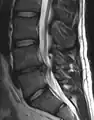

L'imagerie par résonance magnétique peut montrer la hernie, le canal vertébral, les nerfs, les tissus environnants. Les tissus mous sont les mieux analysés par cet examen qui est le plus performant pour le diagnostic de hernie discale. Les images pondérées en T2 montrent clairement la hernie.

IRM cervicale sagittale montrant une hernie discale de niveau C6-C7.